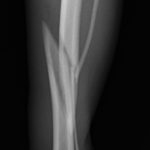

脛骨中央部らせん状骨折 階段で転んだワンチャンが、骨折をしてしまったので手術をしてほしいとの連絡があり対応しました。比較的、長い範囲でのらせん状骨折です。2本のポジションスクリューとプレーティングにより骨接合術を行いました。 症例カテゴリー 放射線治療整形外科軟部組織外科脳神経外科内科腫瘍外科救急・集中治療リハビリテーション科腫瘍内科内視鏡科脳神経科呼吸器外科中医・漢方猫の腎移植循環器科